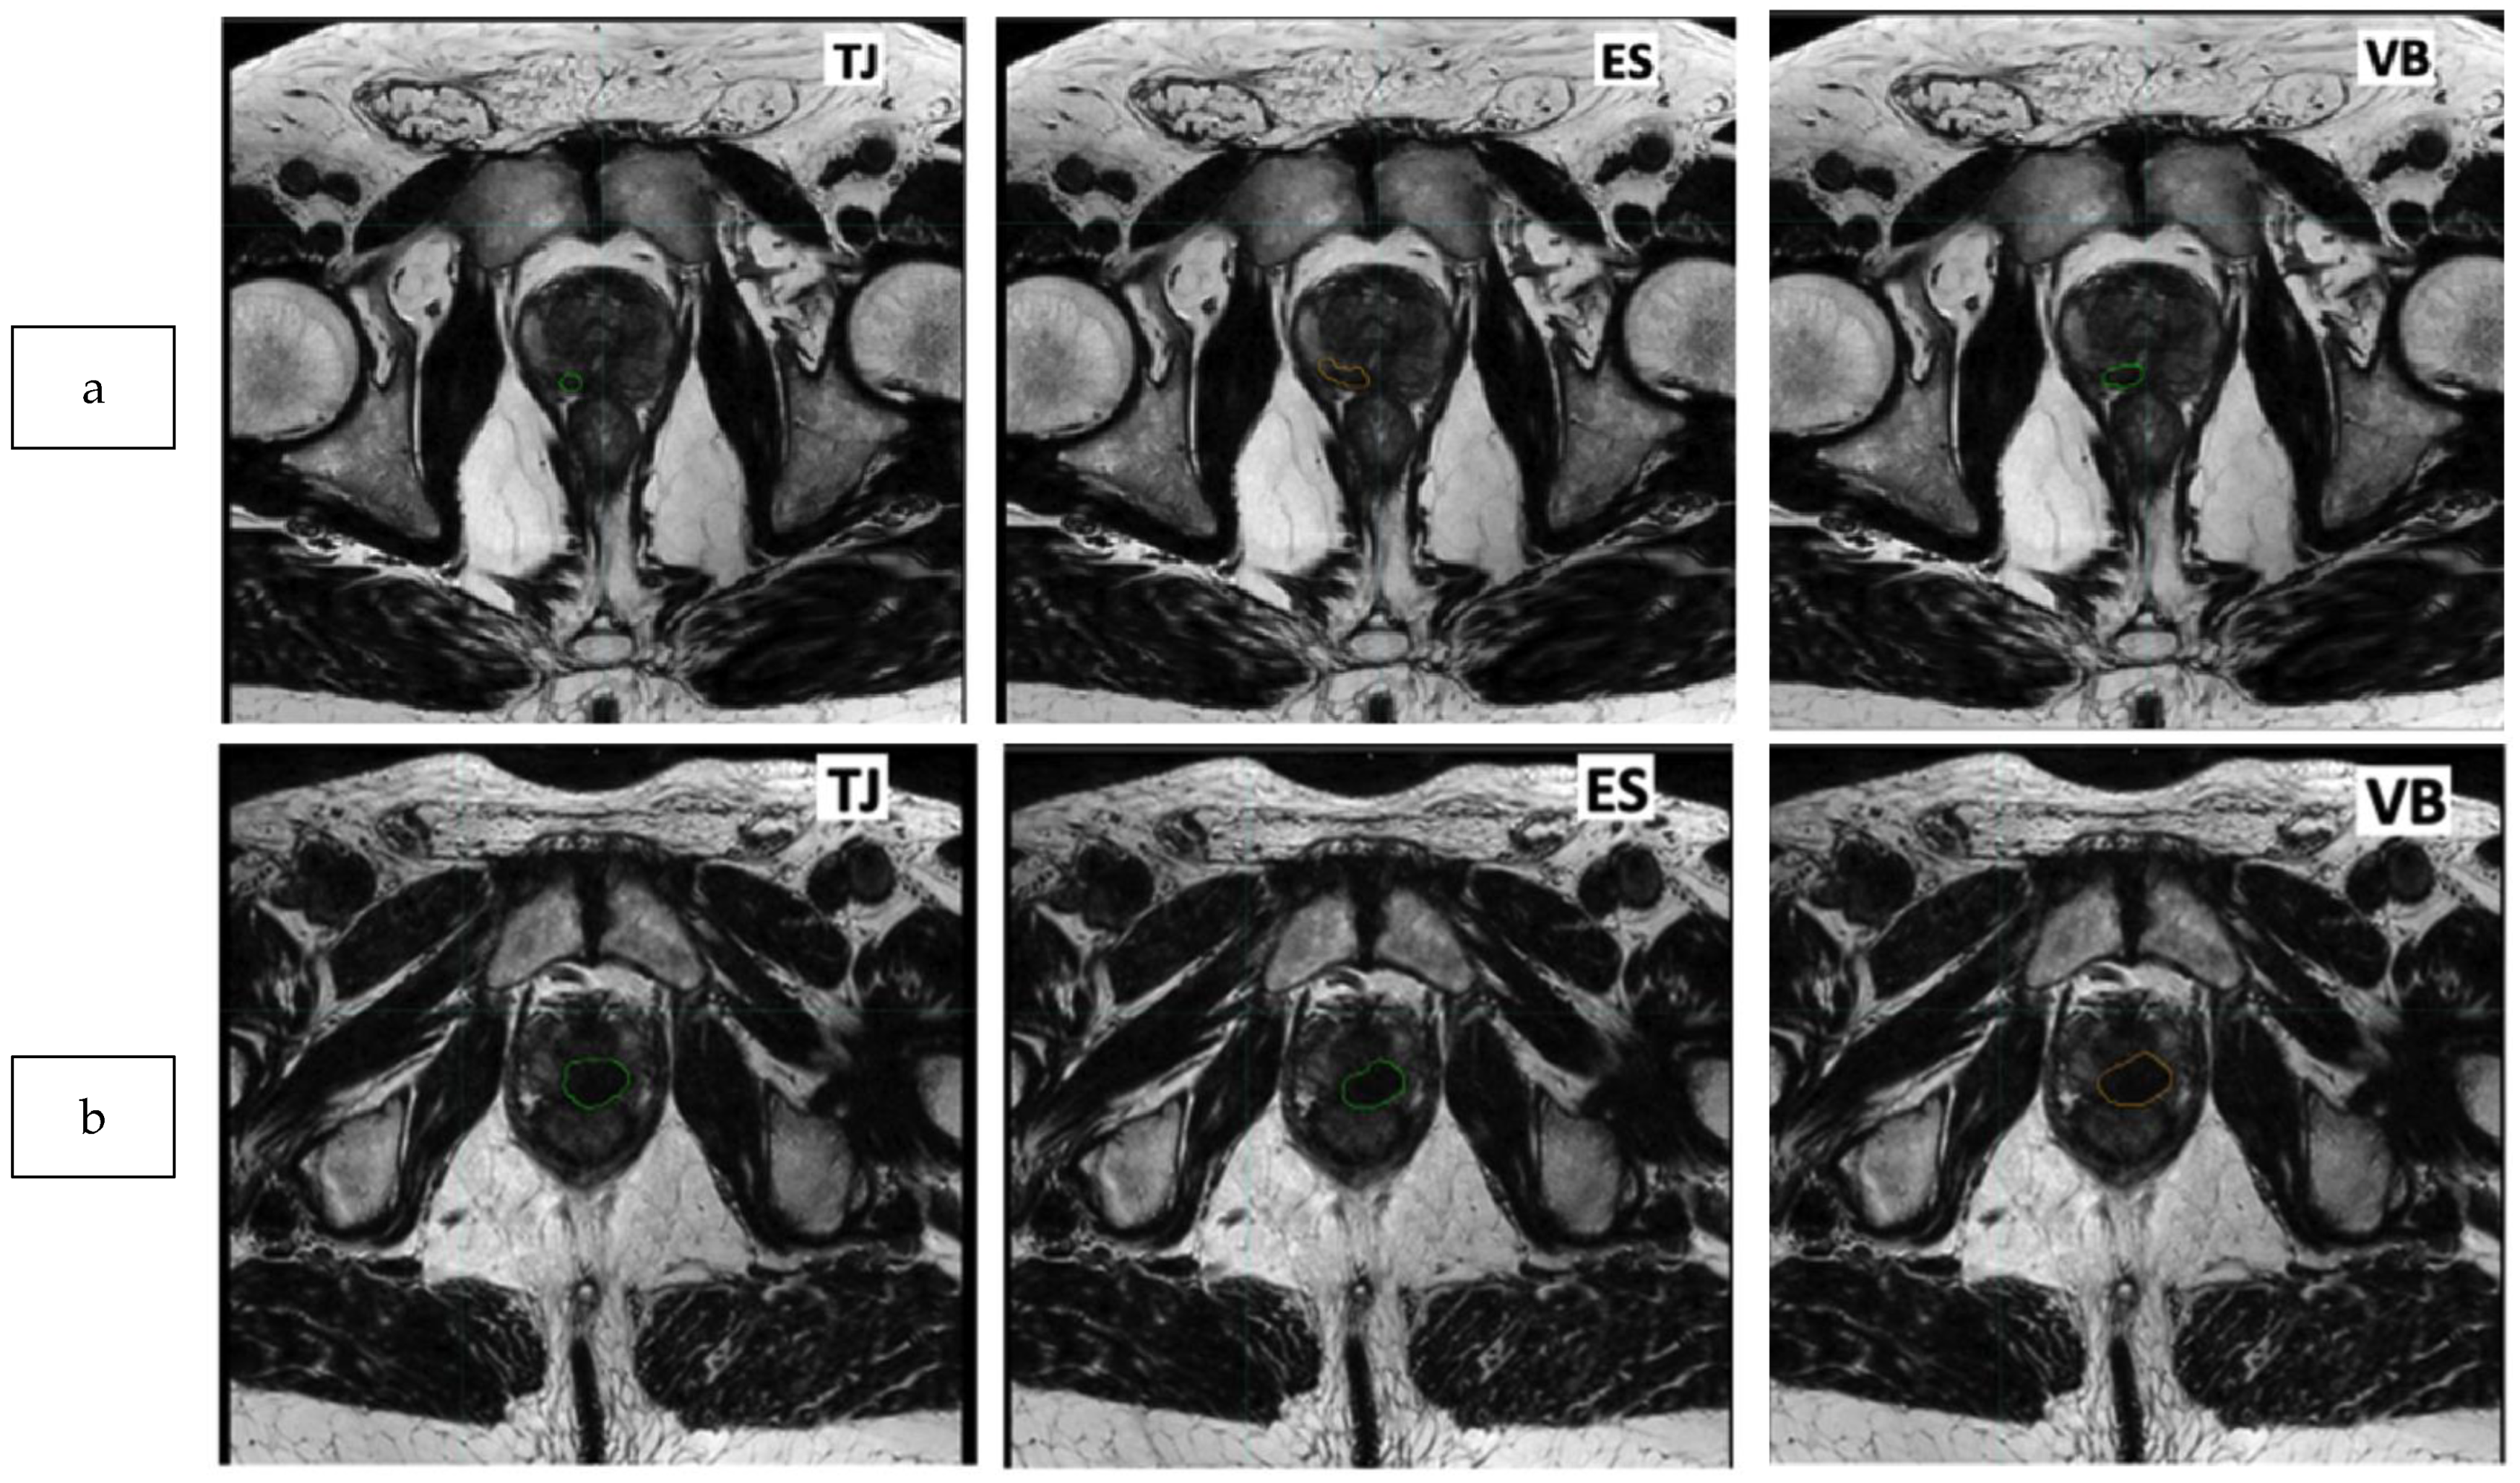

2.3. Delineation of the Dominant Index Lesion (DIL)